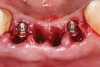

Preoperatively, 1 g of amoxicillin was administered. Using local anesthesia (lidocaine 1:100,000 epinephrine), extractions of teeth No. 23 to No. 26 were performed without raising a flap and with gentle luxation to preserve the remaining facial osseous plate. The sockets were curetted prior to implant placement. A vacuum-formed surgical guide, fabricated based on a diagnostic wax-up of the desired tooth positions for the subsequent fixed prosthesis, was used during implant placement. Osteotomies were performed at sites No. 23 and No. 26 and positioned toward the lingual aspects of the sockets (Figure 3A and Figure 3B). Two tapered implants (OsseoTite™ 313, BIOMET 3i™, Palm Beach Gardens, FL) measuring 3.25 mm x 13 mm were placed. Conical prosthetic abutments (3-mm height) were used to facilitate joining the two implants in a screw-retained fixed partial denture (Figure 4). A laboratory-processed acrylic-resin provisional restoration was altered to allow connection to the temporary cylinders. The provisional was placed into the vacuum-formed surgical guide that was now used to maintain the provisional in the correct 3-dimensional position (Figure 5) while being attached to the temporary cylinders with acrylic resin intraorally. Once a sufficient amount of acrylic resin was placed to secure the cylinders to the provisional, it was removed from the mouth and its contours were completed at the laboratory bench (Figure 6A). The two central incisor sockets were grafted with small-particle allograft material (Puros® Allograft, Zimmer Dental, Carlsbad, CA) to maintain gingival architecture beneath two ovate pontics (Figure 6B). The provisional restoration was inserted and the screws tightened to 20 Nt-cm of torque.